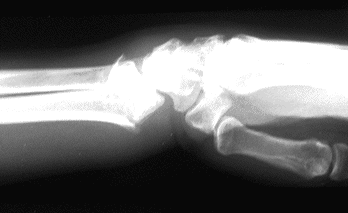

Case 1 Injury